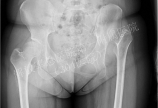

患者,女性,23岁,左下肢跛行20余年。  骨盆X线片显示:左髋关节高位脱位。  下肢全长片显示:左下肢相对短缩。  髋造影MR片显示:左股骨头软骨质量欠佳。